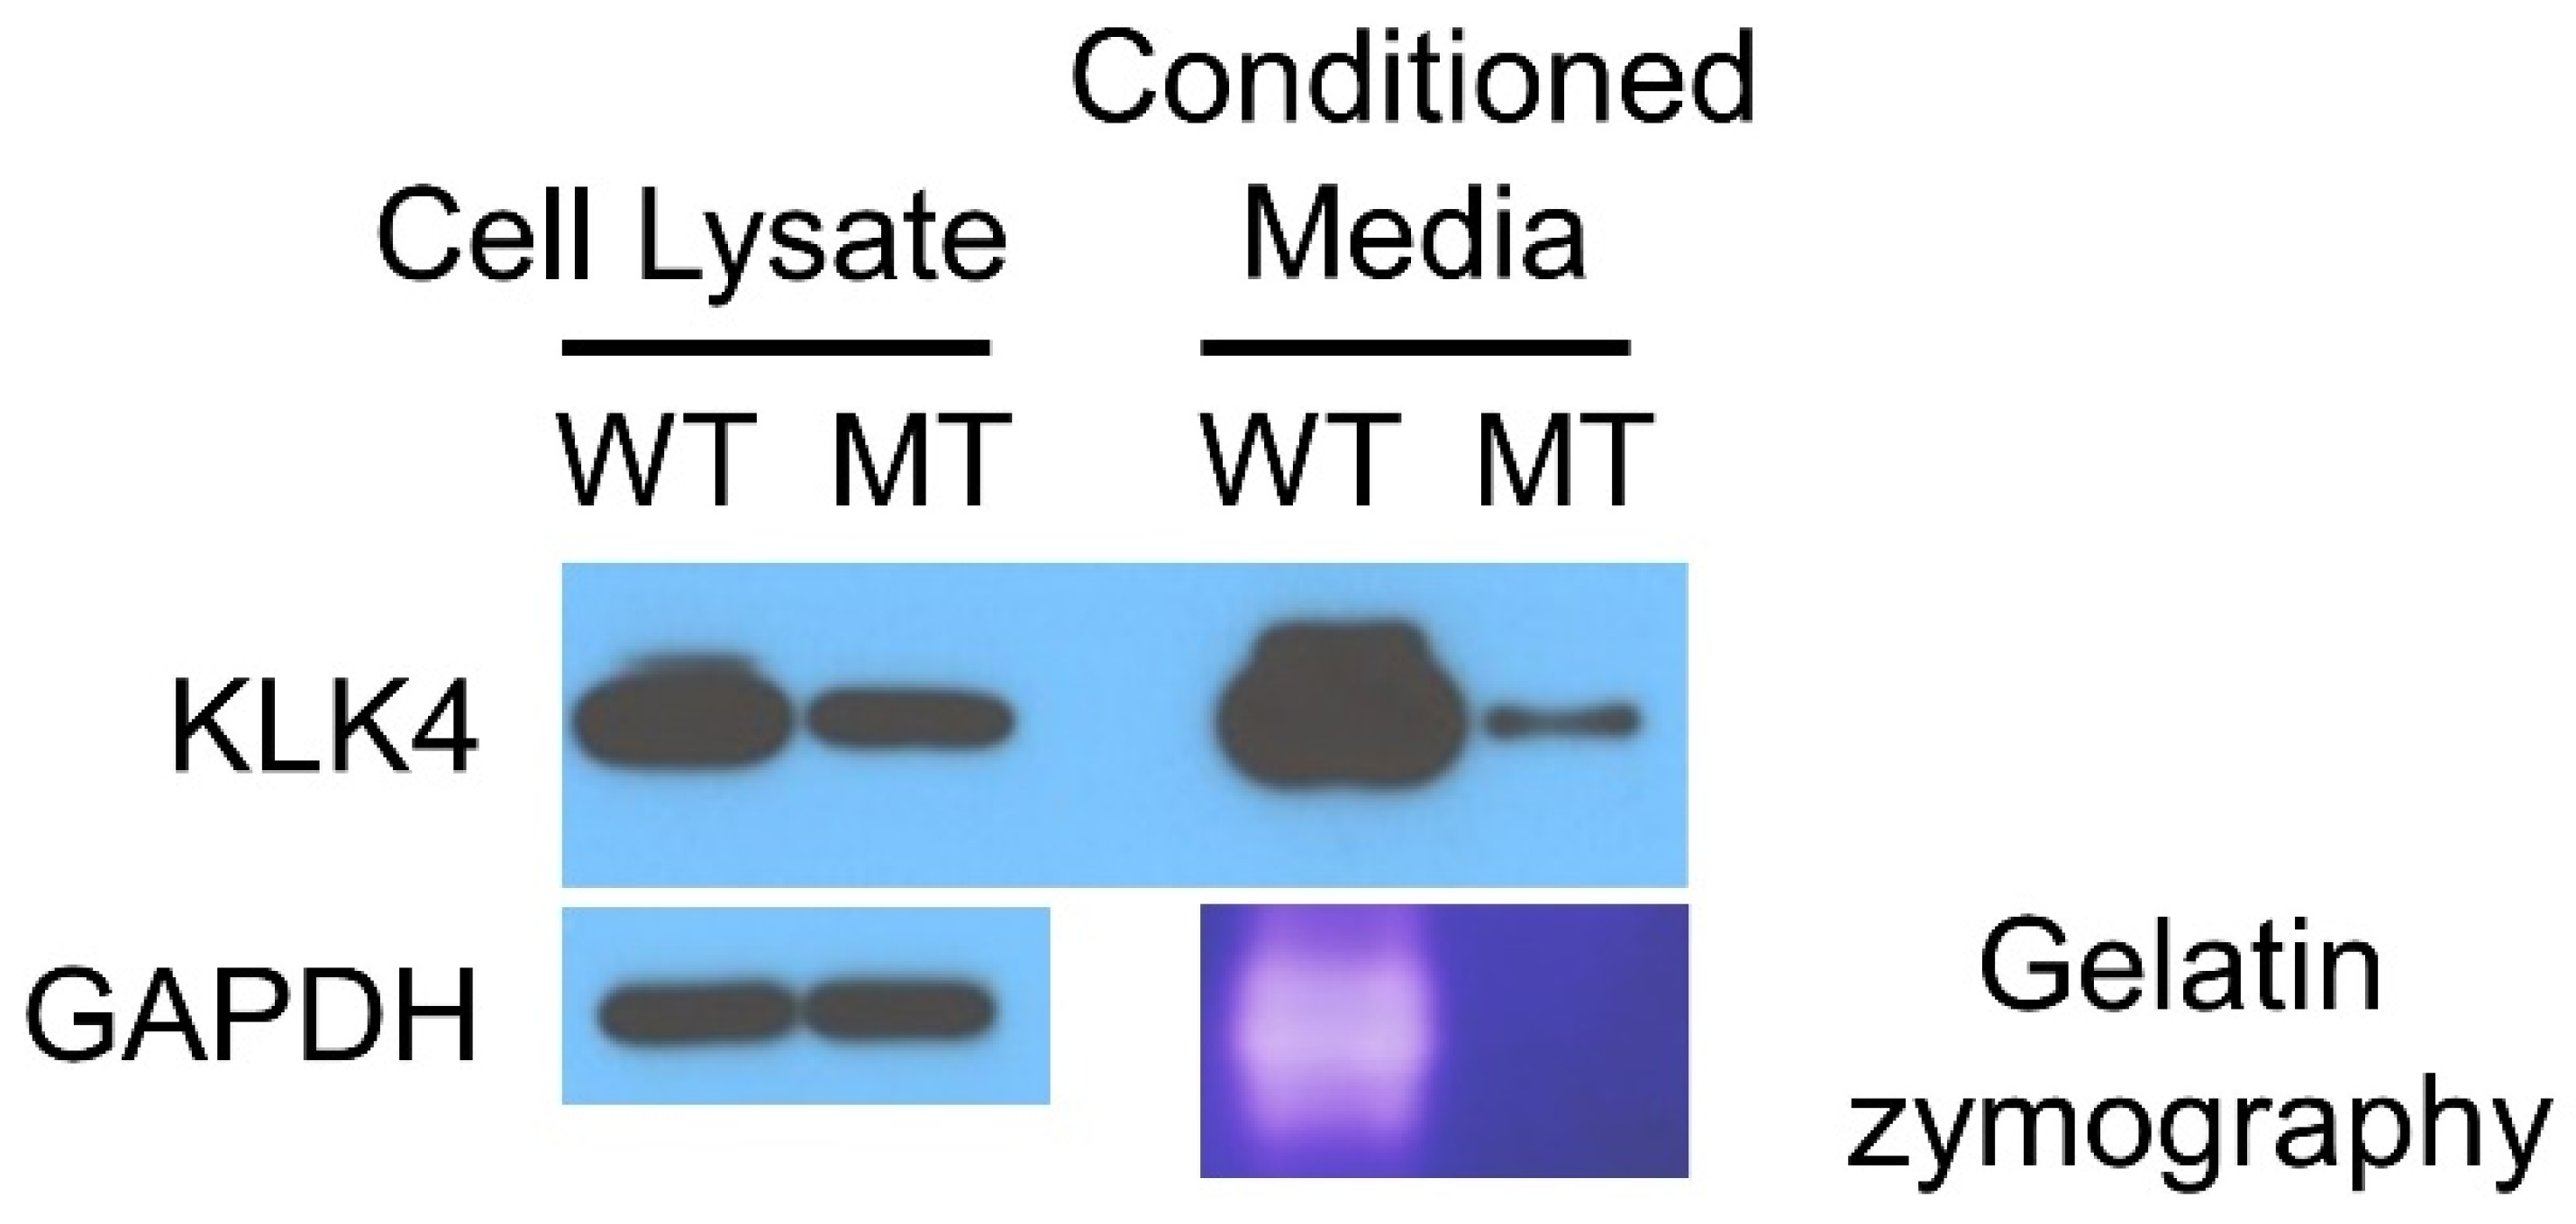

4. Discussion